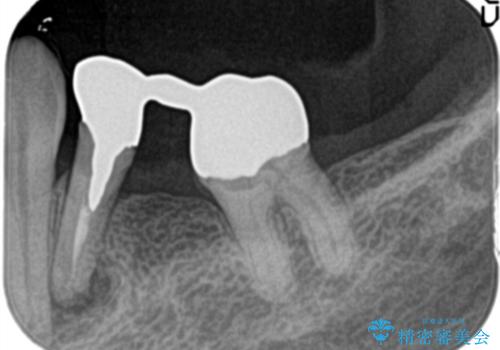

金属のかぶせ物をセラミックへ 根管治療からの再治療

左側の上下の奥歯に適合が悪く、レントゲン上でも根の治療が必要なところがありました。

再治療を行いました。

根管治療からの再治療を行ったことにより、治療期間が多少長くなりましたが、今後再治療の必要性があまりないような、精度の高い治療ができました。